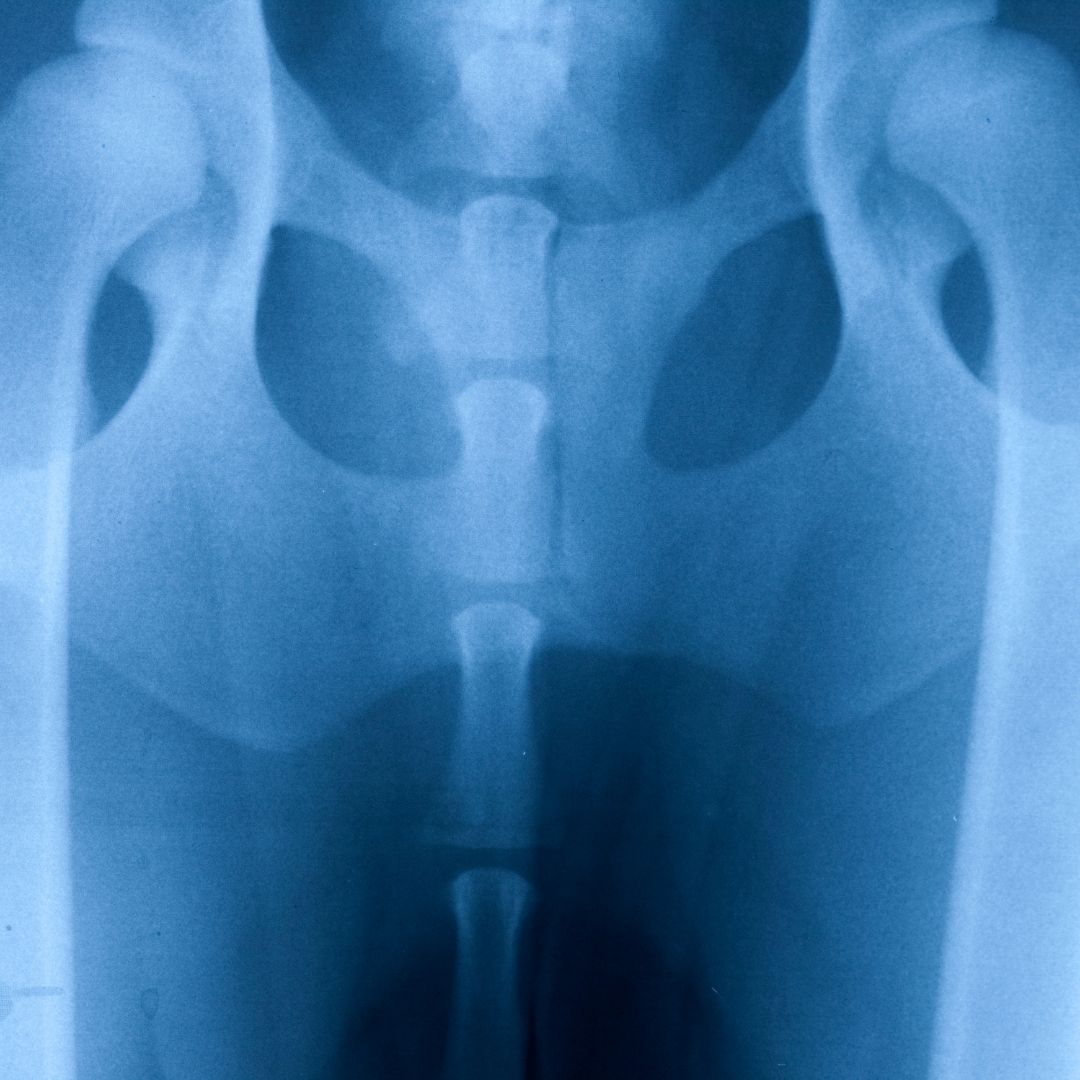

Certain large breeds like the Newfoundland, Saint Bernard, Old English Sheepdog, Rottweiler, German Shepherd, Golden Retriever, Labrador Retriever, and Samoyed are also predisposed to joint issues like arthritis and hip dysplasia (malformation of the hip joint).

While older dogs and certain breeds are more susceptible to joint issues, including arthritis, the condition can affect any dog – so it’s never too early or too late to start thinking about your furry friend’s joint health. The right diet (one that reduces inflammation) combined with a healthy lifestyle will strengthen your dog’s joints and help them live a comfortable and happy life. Let’s explore joint issues in dogs, and how diet and lifestyle can help, below.